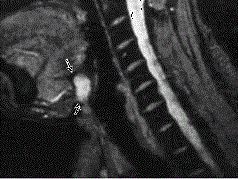

八岁患者,男性,因颈前正中包块6年入院,查体:颈前正中舌骨下方可触及一圆形包块,囊性,无压痛,随吞咽上下活动。患者肿块图像及影像学检查结果见下图,本患...

问题 八岁患者,男性,因颈前正中包块6年入院,查体:颈前正中舌骨下方可触及一圆形包块,囊性,无压痛,随吞咽上下活动。 患者肿块图像及影像学检查结果见下图,本患者应考虑为 ( )

选项 A、鳃裂瘘管 B、甲舌瘘管 C、鳃裂囊肿 D、甲舌囊肿

答案 D